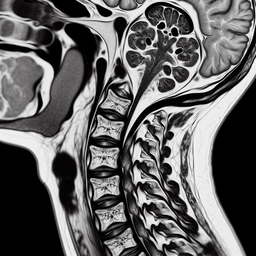

1. **Грижі міжхребцевих дисків** – виявлення випинання дисків, що можуть здавлювати нерви.

2. **Остеохондроз** – зміни в структурах хребта, такі як стирання міжхребцевих дисків.

3. **Стеноз спинномозкового каналу** – звуження каналу, що може здавлювати спинний мозок чи нервові корінці.

4. **Травматичні ушкодження** – визначення ступеня пошкодження після травм.

5. **Пухлини** – виявлення можливих новоутворень.